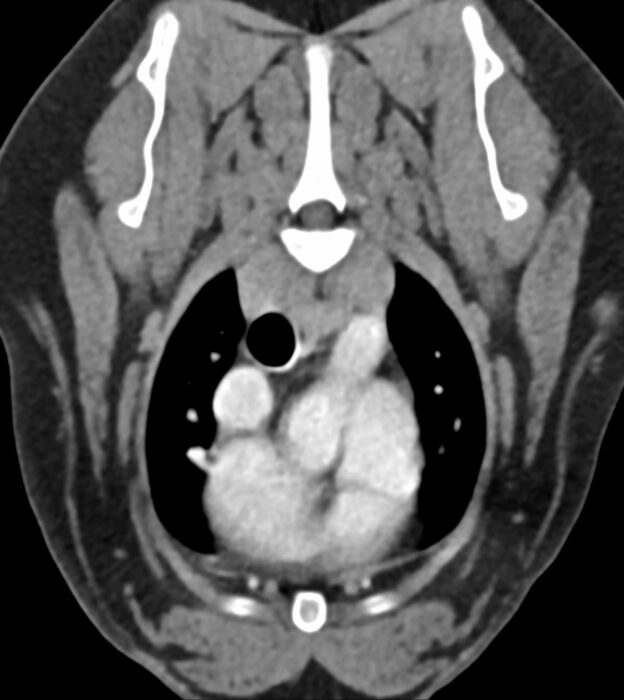

FallbeispieleArbeitsproben & BeispielbefundeAllCTEchokardiographieExoten, Vögel & HeimtiereHund & KatzeMRTRöntgen Frz. Bulldogge, Freya, 10 Jahre Hund & Katze, CT Frz. Bulldogge, Sammy, 9 Jahre Hund & Katze, CT EKH Napoleon, 5 Jahre Hund & Katze, Röntgen Labrador Bella, 9 Jahre Hund & Katze, CT EKH Lucy, 8 Jahre Hund & Katze, Röntgen EKH Charly, 12 Jahre Hund & Katze, Röntgen Staff. Terrier Gizmo, 10 Jahre Hund & Katze, MRT DSH Tyson, 2 Jahre Hund & Katze, Röntgen Kl. Münsterländer Samson, 7 Jahre Hund & Katze, CT EKH Max, 5 Monate Hund & Katze, Röntgen DSH Dexter, 8 Wochen Hund & Katze, CT Malteser Lissy, 5 Monate Hund & Katze, Röntgen Mischling Pack, 8 Jahre Hund & Katze, Röntgen Maine Coon Lenny, 5 Monate Hund & Katze, Röntgen Ringeltaube Exoten, Vögel & Heimtiere, Röntgen Irish Setter Thor, 12 Jahre Hund & Katze, MRT EKH Samson, 7 Jahre Hund & Katze, Röntgen Malteser Jimmy, 9 Jahre Hund & Katze, Röntgen Rottweiler, 19 Monate Hund & Katze, Röntgen Rottweiler, 19 Monate, Echokardiographie Hund & Katze, Echokardiographie Ir. Wolfshund Bailey, 1 Jahr Hund & Katze, CT Mischling Lucky, 9 Jahre Hund & Katze, Röntgen Turmfalke Exoten, Vögel & Heimtiere, Röntgen Ihre individuelle Kontaktanfrage. Zum Login-Bereich .